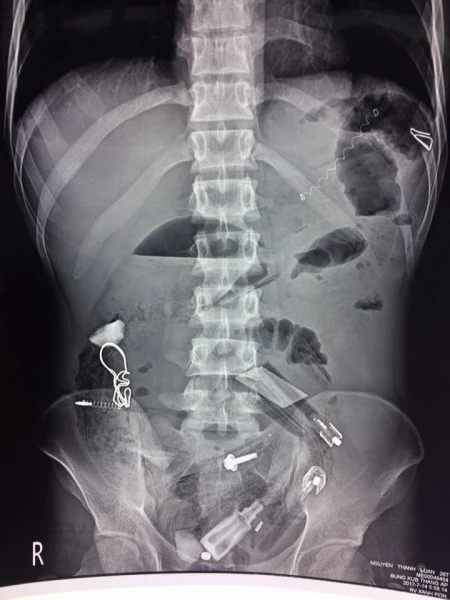

Kết quả chụp X-quang cho thấy trong dạ dày bệnh nhân có nhiều dị vật khác nhau nên các bác sĩ đã chỉ định phẫu thuật. Sau ba tiếng phẫu thuật, các bác sĩ đã lấy ra nào là bút bi, lò xo bút bi, thìa nhựa, lá cây, vỏ kẹo, đinh sắt... từ dạ dày bệnh nhân này. Hiện bệnh nhân vẫn đang tiếp tục được theo dõi tại BV.

Kết quả chụp X-quang cho thấy có rất nhiều dị vật trong bụng bệnh nhân.